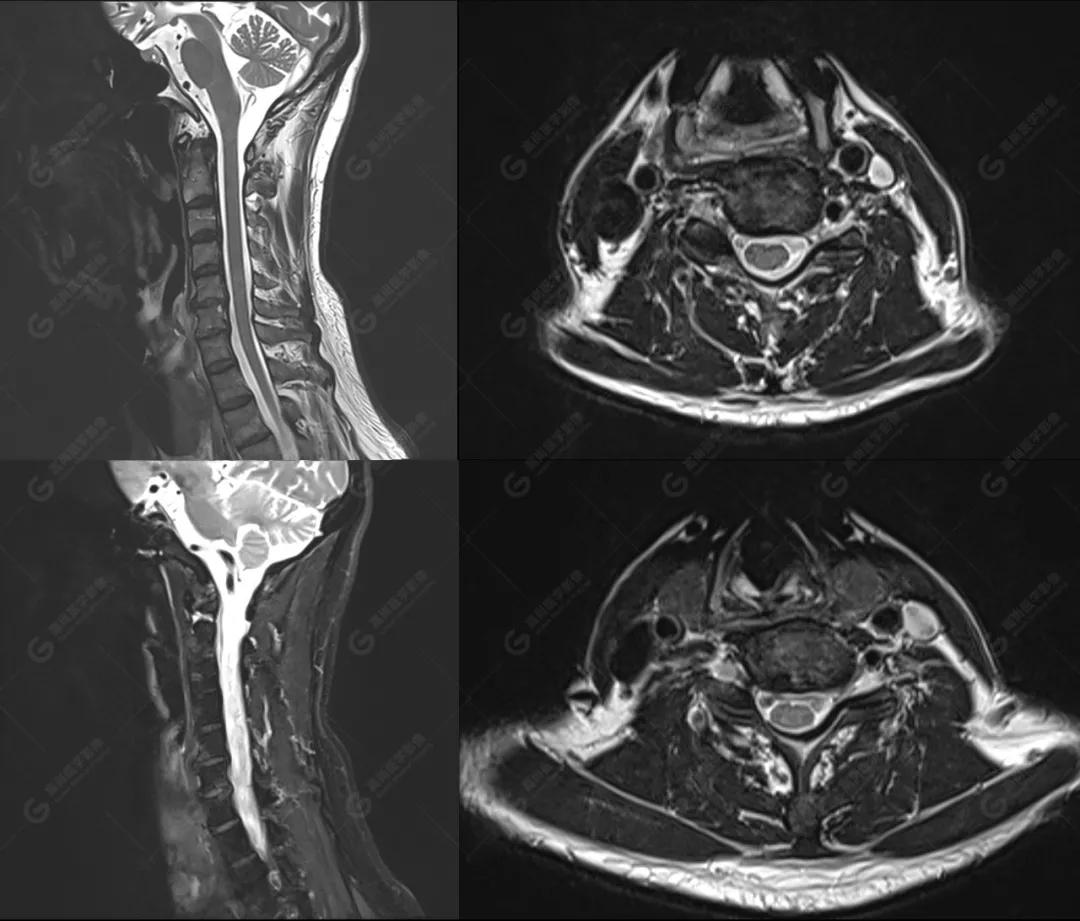

磁共振影像图

图2

影像诊断: 1、颅脑MR平扫未见明显异常。

2、C3/4、C4/5 椎间盘向后中央突出 、C5/6、C6/7 椎间盘膨出 , 相应平面蛛网膜下腔受压, C5/6、C6/7水平 右侧神经根出口稍变窄 ;颈椎右侧上部神经根袖区少许T2高信号,请结合临床。

3、颈椎退行性改变。4、双侧上颌窦粘膜下囊肿。